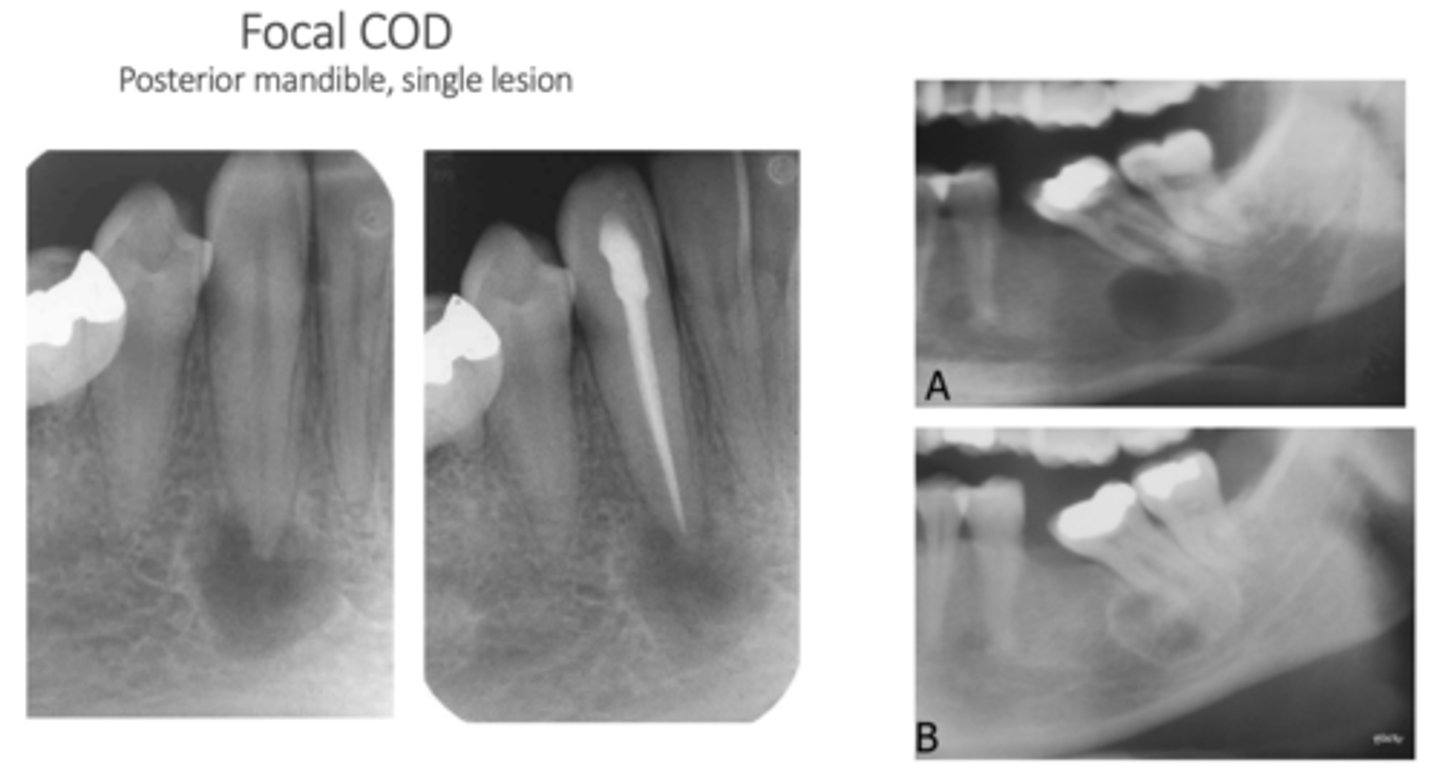

What is a key characteristic of the Focal type of Cemento-osseous Dysplasia?

Different demographic